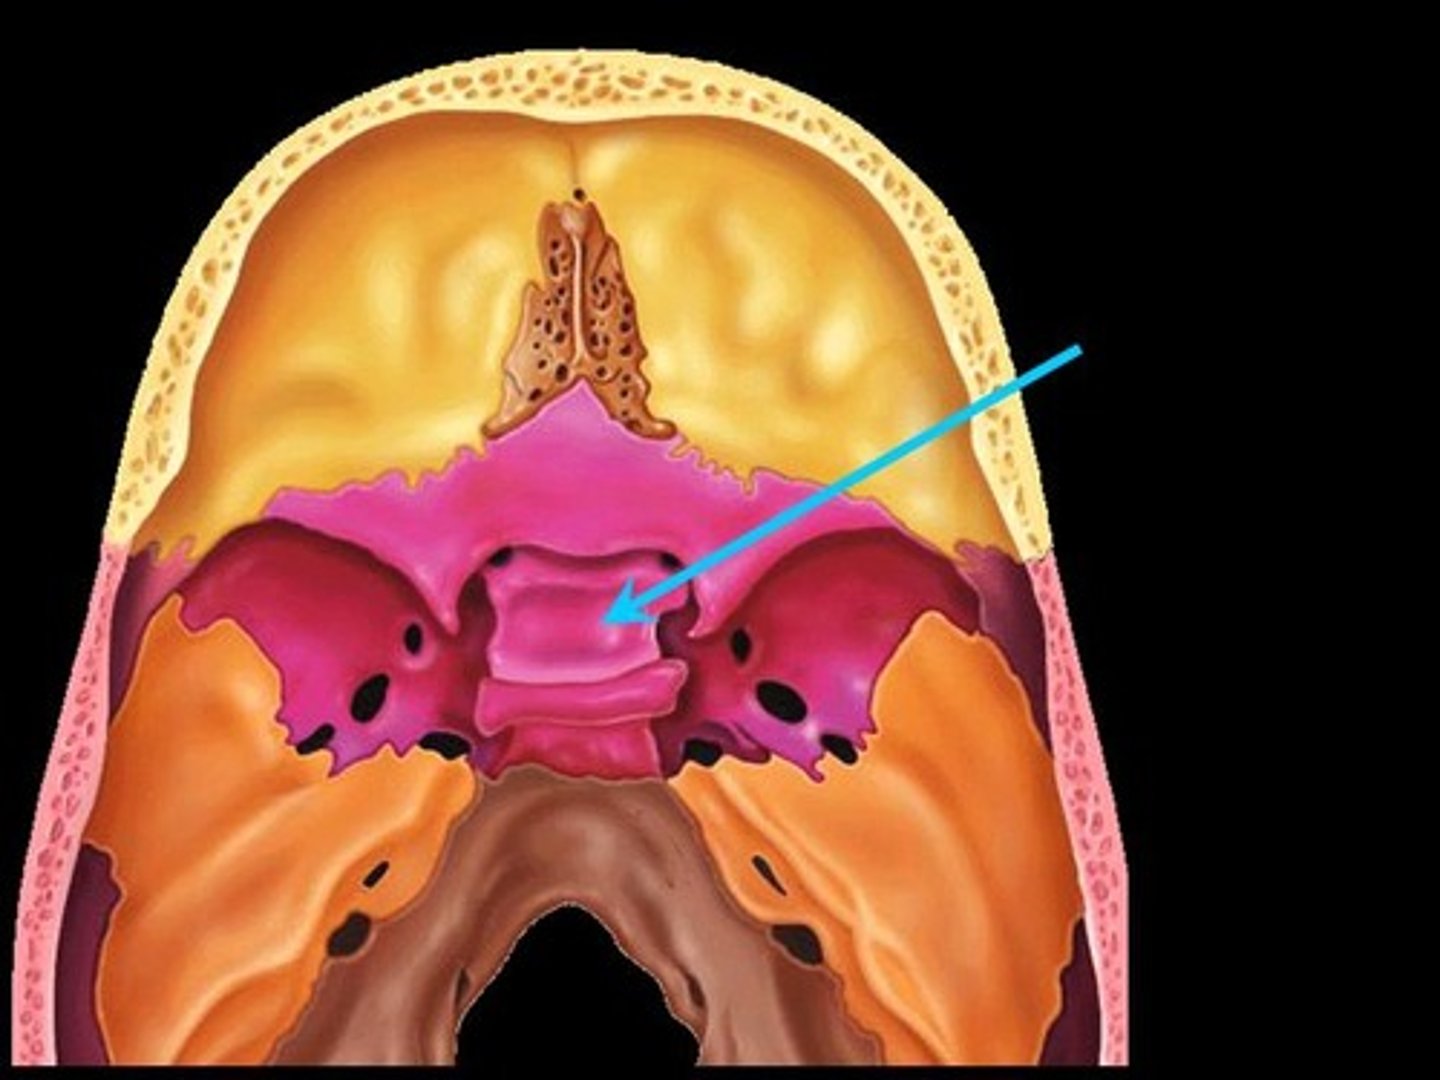

Sella turcia (hypophyseal fossa)

Greater wings

Less wings

Cribiform plate

Crista galli